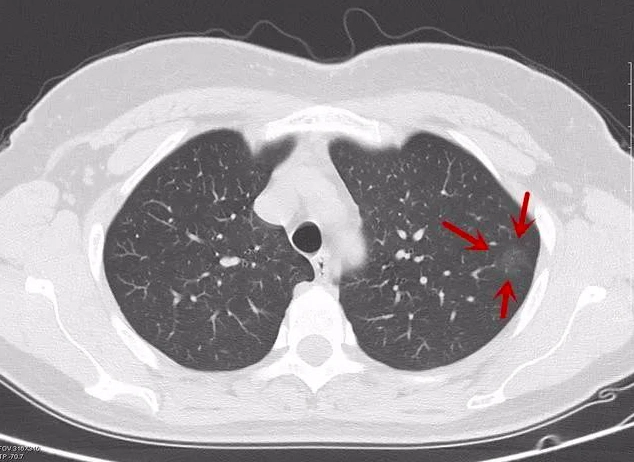

看不懂ct图像?各种类型肺癌典型表现!